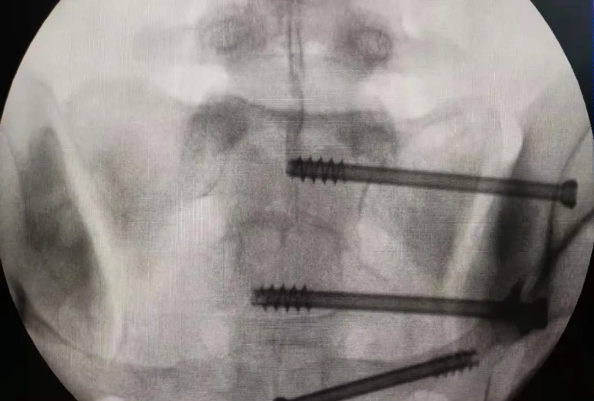

在南昌市第一医院廖琦教授向导下,由创伤骨科团队借助天玑?骨科手术机械人为患者“量身定做”最理想、最清静的教科书般的通道,完善清静微创完成手术,并且手术时间显着缩短,真正做到“指哪儿打哪儿”!更让患者定心的是,天玑?骨科手术机械人的“稳固手”机械臂举行精准定位,不必重复探寻。

由于天玑?骨科手术机械人的精准及高效,可以使手术时间显着缩短,因此在骨盆骨折手术后,在廖琦教授指导下,脊柱外科团队使用天玑?骨科手术机械人同样为20岁女性腰椎骨折患者“量身定做”最理想、最清静的教科书般的通道,完善清静微创完成手术,手术不但时间缩短,并且出血和透视镌汰。